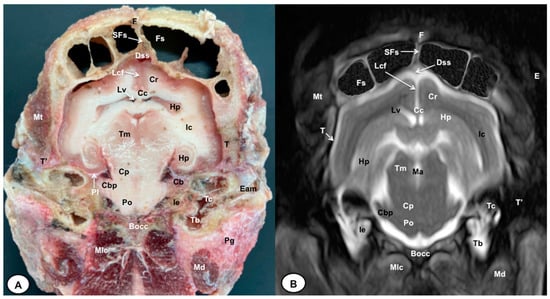

3.1. Anatomical Cross-Sections

3.2. Magnetic Resonance Imaging (MRI)